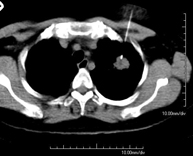

- TC Tórax

Prueba diagnóstica que consiste en obtener imágenes del tórax de alta definición anatómica (pulmones, corazón, mediastino, grandes vasos, caja torácica, etc.) mediante el empleo de un equipo de TC (Tomografía Computarizada). Dichas imágenes se estudian posteriormente en una estación de trabajo que permite reconstrucciones bidimendionales en diferentes planos del espacio y también reconstrucciones 3D (volumétricas). Algunos estudios requieren el empleo de contraste yodado para mejorar la definición de las imágenes.